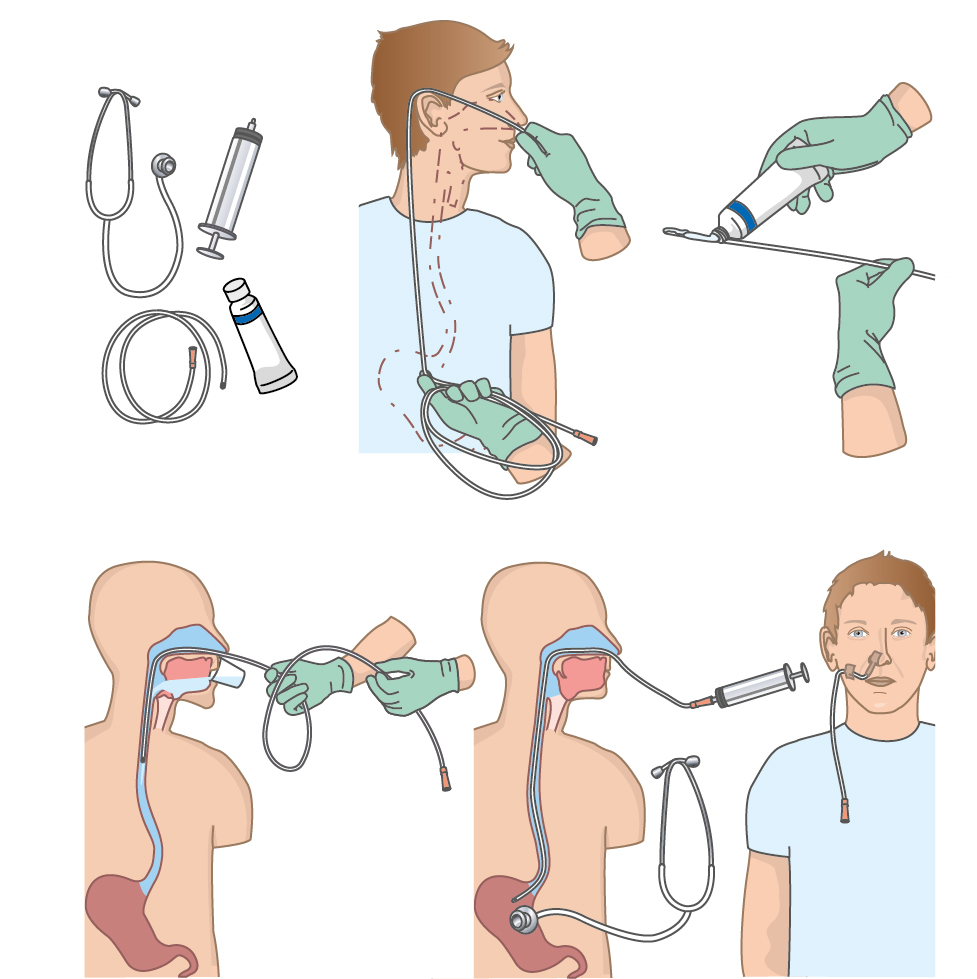

Herzlich willkommen! Ich bin Ihre Expertin für medizinische Illustrationen und kreative Kinderbuch-Illustrationen. Mit einem Auge für wissenschaftliche Genauigkeit und einer Liebe zur Gestaltung kindgerechter Erzählwelten schaffe ich Bilder, die informieren und begeistern. Entdecken Sie mein Portfolio und lassen Sie sich von meiner Arbeit überzeugen!